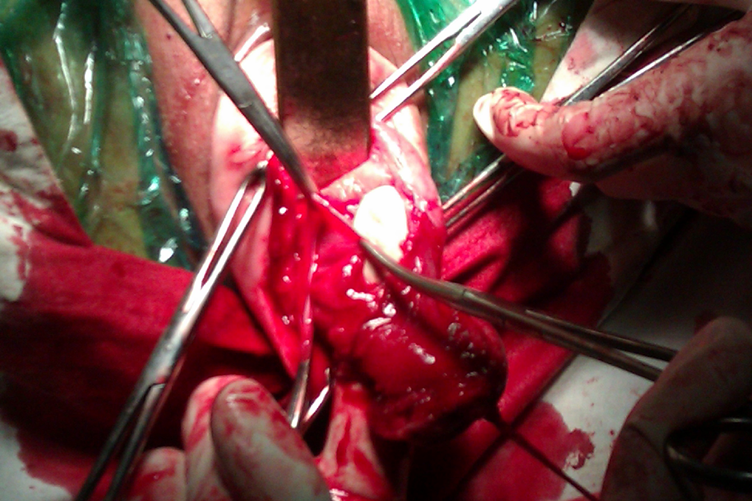

All cases were done under regional anesthesia, either spinal or epidural. All cases were re-assessed in operating theatre after patient was anaesthetized, to see the size, mobility of the uterus, vaginal accessibility and laxity of the pelvic muscles. After cleaning and draping, cervix was held with volsellum. Circumferential incision was made around the cervix, pubo-vesico-cervical ligament was cut and bladder mobilized upwards. Both anterior and posterior pouches were opened one after another. Uterosacral and cardinal ligaments were clamped, cut and ligated. Clamping of uterine vessels was done bilaterally. If at this time the uterine size did not allow an easy exteriorization then debulking techniques like morcellation, bisection, decoring, myomectomy, or a combination of these methods were done. After delivering the uterus in the vagina, hysterectomy was completed in the usual manner. VH was considered successful if it was not converted to the abdominal route.

Majority of the patients had uterine size less than 12weeks 84/100 (84%). Sixteen patients had uterine size between 12-16 weeks. Uterine size wise distribution of patients is given in table 4. Different morcellation techniques like bisection, decoring, myomectomy and debulking techniques were used during the surgery to remove bigger sized Uterus Volume reduction techniques were mostly required for uterine size 12 weeks and above. Debulking techniques were done in 40/100 (40%) patients.